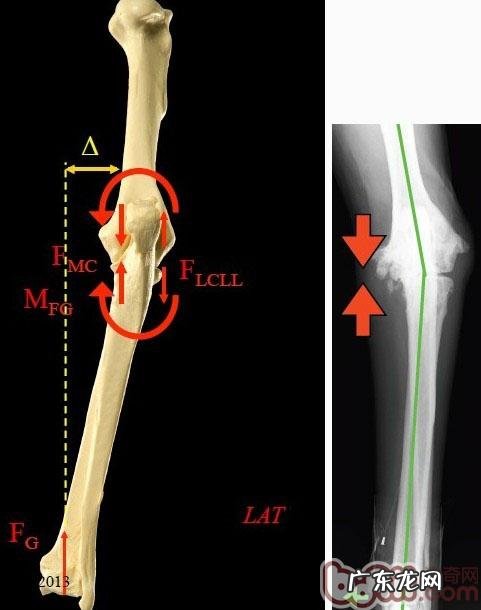

图中是一个小动物的左手 , 从身后看 , 左侧是小动物的里侧 , 右侧是小动物的两侧 。我们可以见到这一小动物座姿像一个气质女人(第一张图右侧的一条狗) , 门把接到人体以内 。我们可以见到这一小动物的腕关节是里侧承受力情况严重 , 两侧是一个打开的能量 。因此 这一骨节承受力都集中化在里侧(图的左边) 。最后 , 这支手便会由于里侧遭受磨坏造成 腕关节发育不全综合征 , 因此便会痛疼坡行 , 进而增长 , 比较严重的会造成骨骼的分离出来和开裂 。

因为腕关节承受力难题造成了一系列的病症和病症 , 因此 在确诊上也必须看腕关节承受力的状况 。一般传统式拍攝x光片的方式是让小狗的手在一定视角下来拍攝x光片 , 以观查小狗腕关节的变病 。可是这类方法不可以体现出小狗腕关节的承受力状况 。依据全新的科研成果 , 大家开发设计并订制了一套使肱骨和桡骨在同一平行线水准表面 , 让前腿承受力的状况下拍攝x光片的专用型保定市专用工具 。用保定市专用工具或是独特保定市方式拍攝出去的x光片更能反映出腕关节的承受力状况 , 为宠物医师临床医学上出示更强的根据 。大家还可以依据腕关节肱骨內外髁与桡尺骨中垂线的承受力状况精确测量出承受力视角(一切正常犬在81.5度上下) 。根据剖析承受力的状况 , 进而制订治疗方案 。